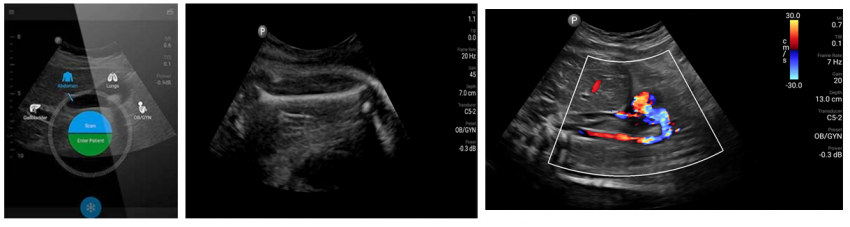

Chison Sonoeye P3 – phased array transducer with a frequency of 1.5 - 4.0 MHz and programs for the abdomen, cardiac, lung examinations.

Chison Sonoeye P5– from 2.0 to 4.5 MHz convex transducer. It has presets and calculations for abdominal, obstetric examinations; presets for lung and abdominal vessels.

Philips Lumify C5-2 - convex transducer with a frequency of 2.0 - 5.0 MHz and a scanning depth up to 30 cm. The program has presets for abdominal, lung, obstetrics and gynecology examinations.